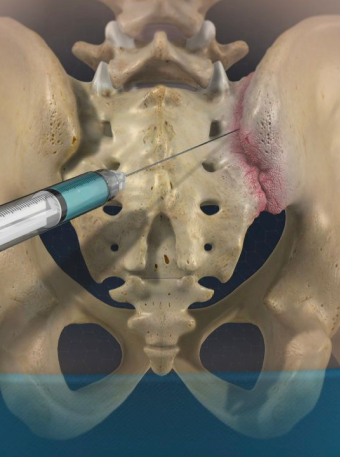

A sacroiliac joint injection is an injection of local anesthetic and a medication into the sacroiliac joint. Due to the numbing medicine used during this procedure, you may experience temporary pain relief afterwards that may last several hours. Once the numbing medicine wears off, however, your pain will most likely return. The medication may give longer lasting pain relief and usually begins working after 24-48 hours.

The first step of the sacroiliac joint injection treatment is applying a local anesthetic to the treatment area. This helps to relieve any discomfort that may occur during the injection process. Once the skin is numbed, an injection will be administered into the sacroiliac joint. You will need to have someone drive you home after the procedure, but you will be able to resume most normal activities immediately following your appointment. Any soreness or bruising from the injection process should fade in a few days.

Your pain may be improved immediately after the injection from the local anesthetic. Once the numbing medicine wears off, your pain may return. It is possible that you will have some soreness at the injection site and your pain may worsen for a day or two after the procedure. The medication takes 2-3 days to start having an effect in most people. Using an ice pack applied three or four times a day can help alleviate the discomfort at the injection site. You may take your usual pain medication after the injection. After your sacroiliac joint injection treatment, you will notice instant relief due to the local anesthetic injected during treatment. Although this will fade within a few hours, the medication should take effect in a few days. At this point, you can expect pain relief that lasts much longer, from anywhere between a few weeks and several months. The duration of the results will vary by patient, but we can help you determine the kind of results you can expect during your initial visit.